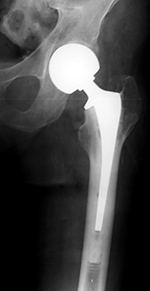

Modular non-cemented total hip prosthesis (THA) |

Implants consist of a proximally porous coated stem and prosthetic head and a porous coated metal acetabular component with a polyethylene liner. From Hunter, 1994 |